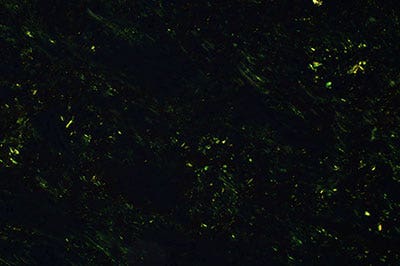

트루컬러 LED(특허출원 중)는 Olympus의 혁신을 위한 헌신의 산물이며, 병리학자에게 익숙한 할로겐램프 및 필터 방식과 같은 연색성 및 광도 성능을 제공합니다. 이 새로운 광원의 고품질 조명은 시중에 나와 있는 밝은 LED로는 달성할 수 없습니다. 이 백색 LED 광원이 탑재된 BX53 현미경은 다른 관찰 방법뿐 아니라 투과 명시야 현미경 검사에도 유리합니다. 강렬한 밝기 수준 덕분에 동시 관찰을 위한 멀티 헤드 논의 및 교육 시스템에 활용할 수 있으며, 연색성이 높은 백색 LED가 신뢰성 있는 샘플 관찰을 원하는 병리학자들이 필요로 하는 색상 무결성 성능을 제공합니다.

그림 6: 26인용 멀티 헤드 토론 시스템(왼쪽)과 관찰 이미지(오른쪽)